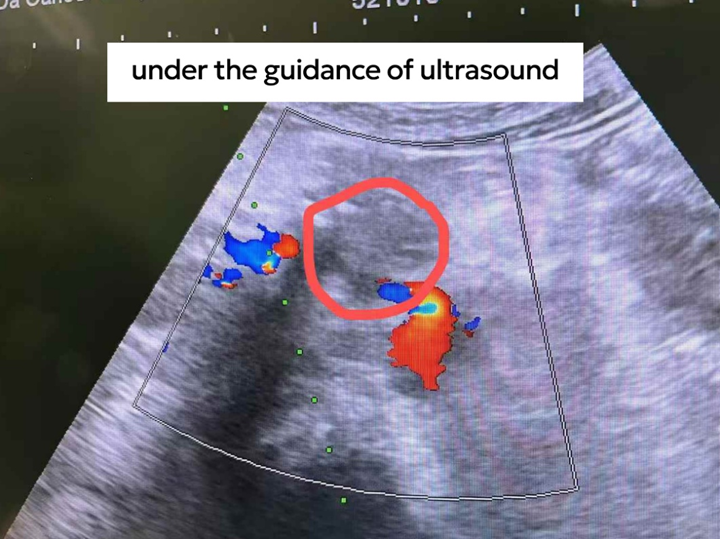

เมื่อเธอเริ่มตระหนักว่าความผิดปกตินี้ไม่ใช่เรื่องเล็ก โมลินจึงเข้ารับการตรวจเพิ่มเติมที่โรงพยาบาล ผลการตรวจอัลตราซาวนด์พบความผิดปกติในตับอ่อน หรือที่เรียกว่า “ก้อนเนื้อ”

หลังผ่านการประชุมวางแผนการรักษาโดยทีมสหสาขาวิชาชีพ ทีมแพทย์แผนกอายุรกรรมมะเร็งที่ 4 ได้ดำเนินการรักษาให้โมลินด้วย การจี้ทำลายก้อนมะเร็งตับอ่อนด้วยมีดนาโน ร่วมกับ การบล็อกปมประสาทช่องท้อง และภายหลังการรักษาได้เสริมด้วย ภูมิคุ้มกันบำบัด